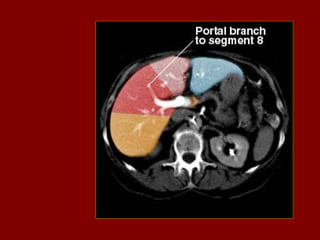

PV(R) Ramo direito da veia porta

INCISÃO SOBRA AVEIA HEPÁTICA DIREITA

INCISÃO SOBRE AVEIA HEPÁTICA MÉDIA.

INCISÃO SOBRE AVEIA HEPÁTICA ESQUERDA.